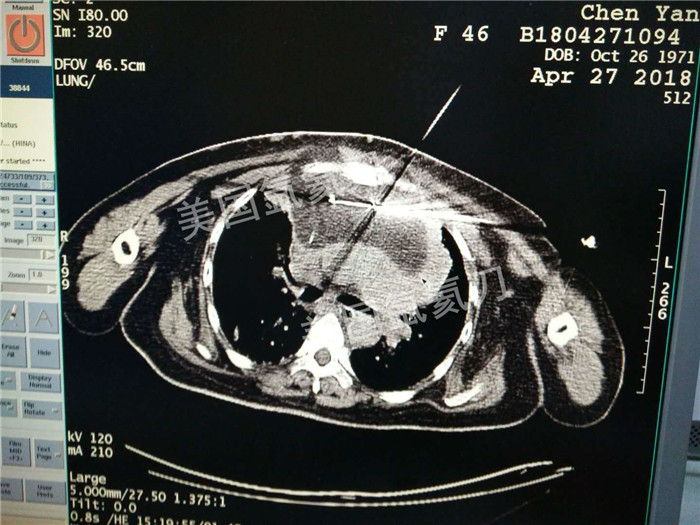

河北省中医院肿瘤科王利民主任胸腺19公分肿瘤氩氦刀手术

图片版权归美国氩氦刀所有,仅用于美国氩氦刀的宣传交流